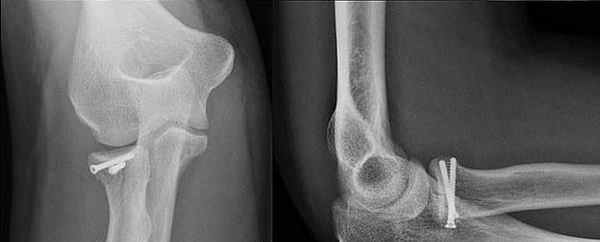

Перелом лучевой кости с вывихом головки локтевой кости (перелом Галеацци) • Причины: падение на вытянутую руку, удары по предплечью • Патоморфология: лучевая кость ломается в нижней трети, её отломки смещаются кпереди (дистальный отломок дополнительно занимает положение пронации из-за сокращения мышц), образуя угол, открытый кзади; головка локтевой кости смещается в ладонную или тыльную сторону • Клиническая картина: характерная деформация (западение на тыльной поверхности предплечья с лучевой стороны и выпячивание на ладонной), искривление оси лучевой кости, пальпируется головка лучевой кости на локтевой стороне лучезапястного сустава, болезненность при пальпации и осевой нагрузке. Надавливание на головку лучевой кости вызывает вправление, при прекращении давления головка снова вывихивается. Необходимо проводить в обязательном порядке рентгенографию с захватом лучезапястного сустава • Лечение: репозиция, гипсовая повязка на 8–10 нед, при неэффективности консервативного лечения — открытая репозиция и остеосинтез лучевой кости, открытое вправление головки локтевой кости.

Переломы Галеацци представляют собой переломами дистального отдела лучевой кости со вывихом дистального лучезапястного сустава.

Вывих головки лучевой кости легко пропустить при переломах Монтеджи, поскольку перелом настолько очевиден, что, в случае выявления перелом проксимального отдела локтевой кости, его необходимо особенно тщательно обследовать. Головка лучевой кости, как правило, видна за пределами ее нормального сочленения с головкой плечевой кости (capitulum). При переломах Монтеджи радиокапителлярная линия (линия, соединяющая шейку лучевой кости и головку плечевой кости), также не выровнена правильно, что указывает на вывих (см. рисунок Передняя плечевая линия и радиокапителлярная линия Передняя плечевая и радиокапителлярная линии ). Если при переломах Галеацци (аналогично переломам Монтеджи) есть перелом дистального диафиза лучевой кости, то легко пропустить вывих дистального лучелоктевого сустава, поэтому на него следует обратить особое внимание.